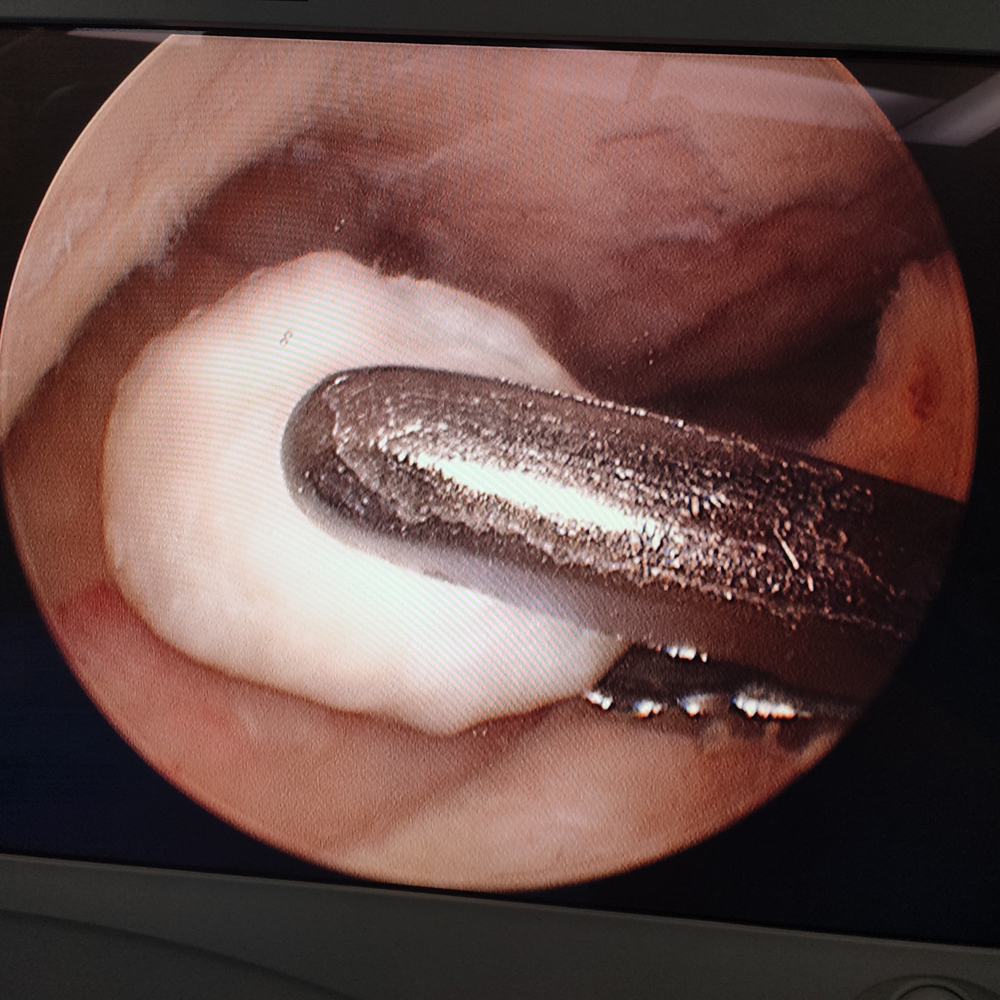

膝关节镜下操作器械取出游离体